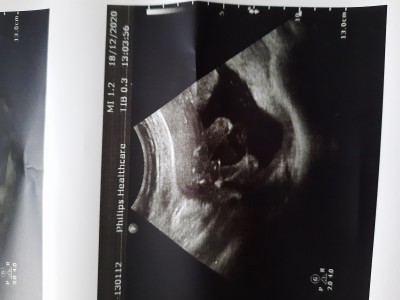

Arkadaslar cinsiyeti 10 gune netleştirelim dedi sizler resimde ne görüyorsunuz tahmin de bulunur musunuz

Gebelik haftası 17

Iste cinsiyet pozisyonu tamda bu şekilde :) bazısı normal ultrason resmi atıp cinsiyet tahmini istiyor yani çocuğun yandan cinsiyeti hic bi şekilde anlasilamaz.. burada bacak arası dolu gibi erkeğe benziyor sayet kordonu değilse :) doktorunuz daha iyi bilgilendirecektir hayırlısı olsun.

Normal ultrason resmi koyup cinsiyeti sizce nedir diye soruyorlar ya.. onu kastediyorum. Bakın misal bu bayanın attığı bacak arasıdır cinsiyete bu şekilde bakılır. Ha doktor belki kemik yapısından vs baska şekilde de anlayabilir ama biz doktor değiliz sonucta anlayamayız.

Bacak arası mı bu? Erkek bence

Aynen bacak arasi alttan cekim galiba

Çok net erkek

17.haftada böyle bir görüntü varsa erkektir kız olsa boş oluyor ama bakalım doktor ne dicekk

Erkek benim oğlanla aynı duruşta aynı pozisyonda aynı pipi ahahah :D